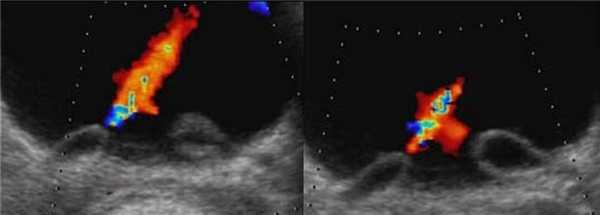

Рисунок. Двустороннее уретероцеле на УЗИ: в режиме ЦДК из верхушек уретероцеле определяется выброс мочи.

Рисунок. На УЗИ в уретероцеле определяется гиперэхогенная структура с акустической тенью — камень. Уретероцеле может являться одним из факторов, способствующих камнеообразованию.